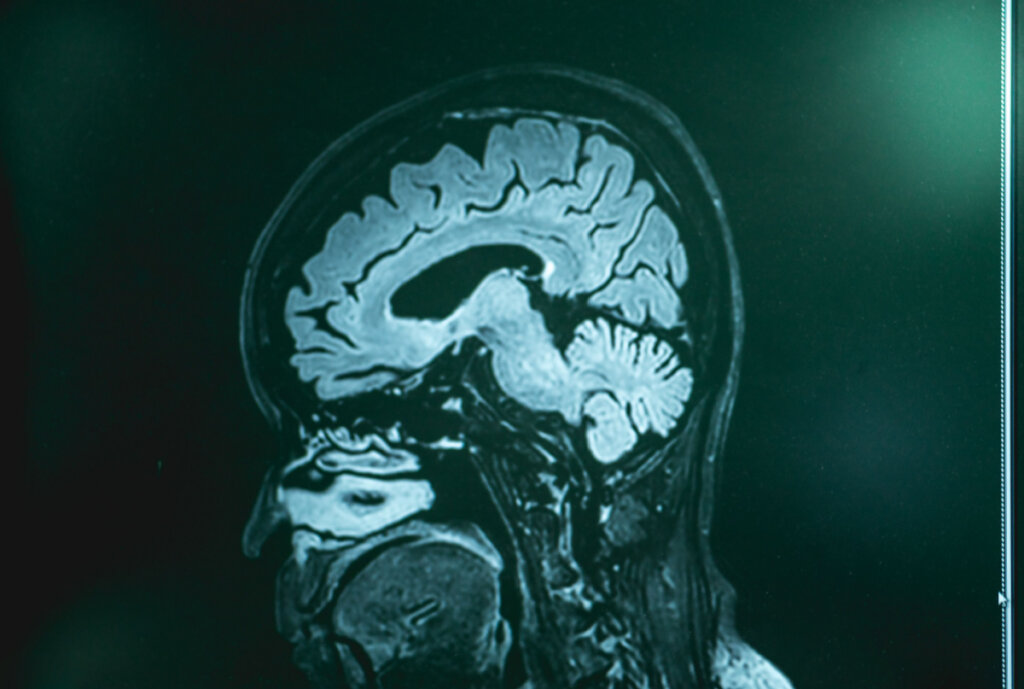

Til tross for uvitenhet om årsak-virkning for denne spesielle typen demens, vurderes ulike hypoteser, noen med større suksess. Gjennom nevroavbildningsprosedyrer kan visse atrofi observeres hos disse pasientene. Med andre ord, krymping av visse områder av cortex, spesielt i tinning- og pannelappen.